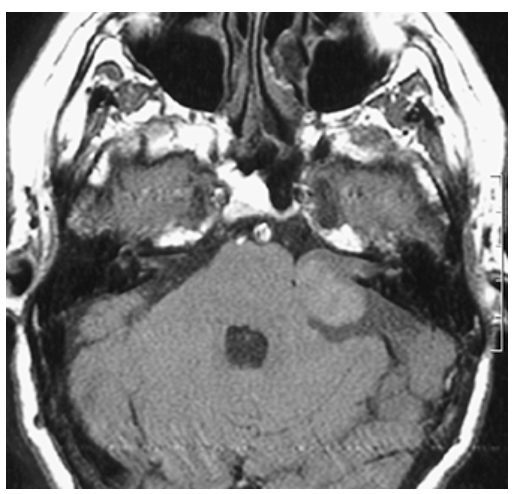

Acoustic Neuroma. Noncontrast T1-weighted axial image demonstrating round isointense mass at the left cerebellopontine (CP) angle.